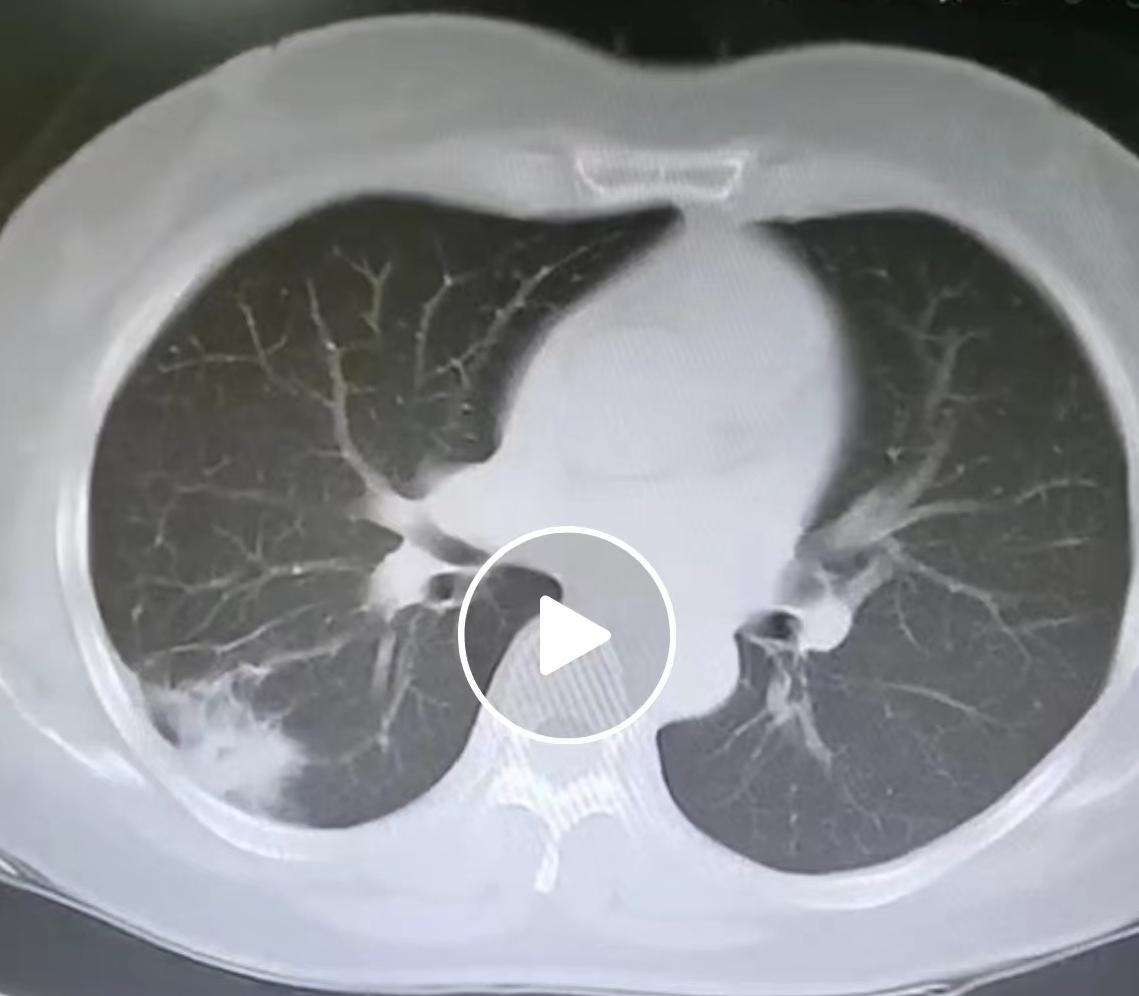

“太可怕了!”浙江宁波,一老人去体检,没想到竟查出肺癌,住院治疗后,32岁的儿子天天在医院陪护,顺便也做了个体检,发现竟然和母亲一样患了肺癌,令人疑惑的是,母子二人之前均没有不适症状,医生的解释令人意外! 69岁的陈阿姨在村里组织的免费体检中,被发现肺部有一个近3厘米的结节。进一步检查后,确诊为肺癌,并在宁波市第二医院接受了根治手术。住院期间,她32岁的儿子小李天天陪护在身边。 看着母亲术后恢复得不错,小李想着“闲着也是闲着”,顺便给自己也做了个胸部CT检查。这个无意间的决定,却意外发现他的肺部也存在一个12毫米的磨玻璃结节,同样被确诊为早期肺癌。令人后怕的是,母子二人在确诊前,都没有咳嗽、咳血等任何典型不适。 肺癌本身不直接遗传,但存在明显的家族易感性,如果直系亲属患有肺癌,其他家庭成员在遗传上可能对致癌因素更敏感,患病风险会比普通人高出2至3倍。这种风险叠加共同的生活环境(如潜在的二手烟、厨房油烟等)和相似的生活习惯,导致了风险的成倍增加。 早期肺癌之所以常常“静悄悄”,是因为肿瘤体积小、生长在肺部外周地带,未对关键组织和神经造成压迫,加之肺部强大的代偿功能,使得患者早期可能毫无察觉。正因如此,定期进行低剂量螺旋CT筛查,对于有家族史的高危人群至关重要,它是发现早期肺癌最有效的手段。 万幸母子俩的癌症都发现得非常早,经过手术治疗后,效果很好,两人均无需进行放化疗,只需定期复查即可。一次体检和一次“顺便”的检查,挽救了一个家庭。 一个人的确诊,应当成为所有近亲的健康警示灯,主动进行早期筛查,是应对家族易感性最有效的方式。 各位读者你们怎么看?欢迎在评论区讨论。信息来源:《69岁母亲做肺癌手术,32岁儿子陪护时顺手拍CT也查出肺癌,母子均无症状,医生:肺癌具有家族易感性。》荆楚网